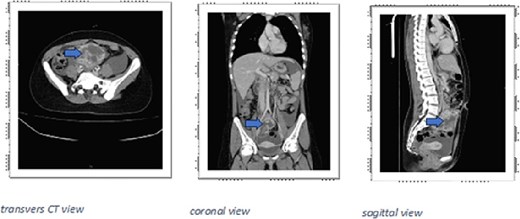

A CT scan of the abdomen and pelvis revealed a large right pelvic ill-defined heterogeneously enhancing solid-cystic mass, with hyper density in non-contrast study, represents hemorrhage, measuring about 9 × 9 × 9.5 cm (AP × TS × CC diameter), the mass located below the aortic bifurcation and slightly compressing the right iliac vessels, associated with moderate ascites in the abdomen and pelvis (Fig. 1).

CT scan large right pelvic ill-defined heterogeneously enhancing solid-cystic mass (arrows), with hyperdensity in non-contrast study, represents hemorrhage, measuring about 9 × 9 × 9.5 cm (AP × TS × CC diameter), the mass located below the aortic bifurcation and slightly compressing the right iliac vessels.